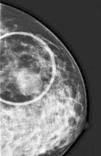

We report the case of a 46-year-old female, with no medical history of interest, who consulted due to the appearance of a 4-cm tumor in the left breast of six months of evolution. We proceeded with the study, making radiological imaging (mammogram and magnetic resonance) and histopathological investigations. The examinations conducted, including blood count, biochemistry, serologies, and tumor markers, were normal highlighting slightly elevated ¿2-microglobulin levels (2.9mg/L). Mammography and magnetic resonance findings were suggestive of breast cancer. Histological examination showed a tumor composed of a large-sized cell infiltrate, with scarce cytoplasm, irregular nuclear membrane, split cells with prominent nucleoli, and numerous mitoses. The immunohistochemical study showed positivity for tumor populations CD19, CD20, CD79a, PAX-5, bcl-2, bcl-6 and MUM-1 and focally for CD10 and negativity for cyclin D1 and CD38 (Figure 1). Ki 67 was 80%. Given the combination of clinical, histopathological, and immunohistochemical findings, a diagnosis of primary diffuse large B-cell non-Hodgkin lymphoma was established, warranting an extended study with a cervico-thoraco-abdomino-pelvic scan and bone marrow biopsy to rule out lymphadenopathies and bone marrow infiltration. With the diagnosis of primary diffuse large B-cell non-Hodgkin lymphoma, chemotherapy was established using the R-CHOP scheme (rituximab, cyclophosphamide, adriamycin, vincristine and prednisone).

PBL is a rare entity in everyday medical practice. Initially described by Gross in 1880, it is about 0.4–0.5% of all malignant breast tumors and 0.38–0.70% of non-Hodgkin lymphomas,2 with the most common subtype being diffuse large B-cell non-Hodgkin lymphoma. It is characterized by the appearance of a unilateral breast mass particularly in the upper quadrant of the right side. The incidence increases with age. Patients with PBL infrequently present with signs of skin edema, retraction, erythema, and nipple involvement. Although its etiology is unknown, its association with different processes, among which are estrogen and autoimmune diseases,3 has been described; none of these associations were found in our patient. Other entities that present with similar breast swelling and symptoms should be considered in the differential diagnosis. To do this, clinicians rely on a detailed anamnesis, and complementary analytical and imaging studies (Figure 2). The diagnosis, regardless of the clinical data provided by the patient and the exclusion of other entities, is established when a consistent histological pattern is demonstrated.